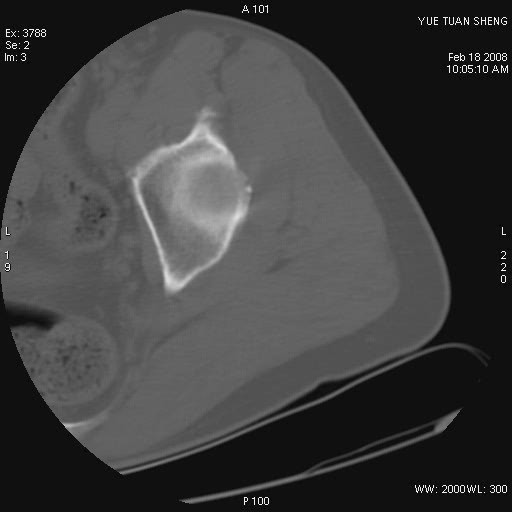

患者,男,56岁,左髋部疼痛1个月,x线:左股骨头高密度影,性质待定,右侧正常。左髋ct如图

左股骨颈区椭圆形磨玻璃样影,边缘明显硬化环环绕,其内见斑点状类钙化高密度影考虑 良性骨病-----骨纤,骨化性纤维瘤,内生软骨瘤。